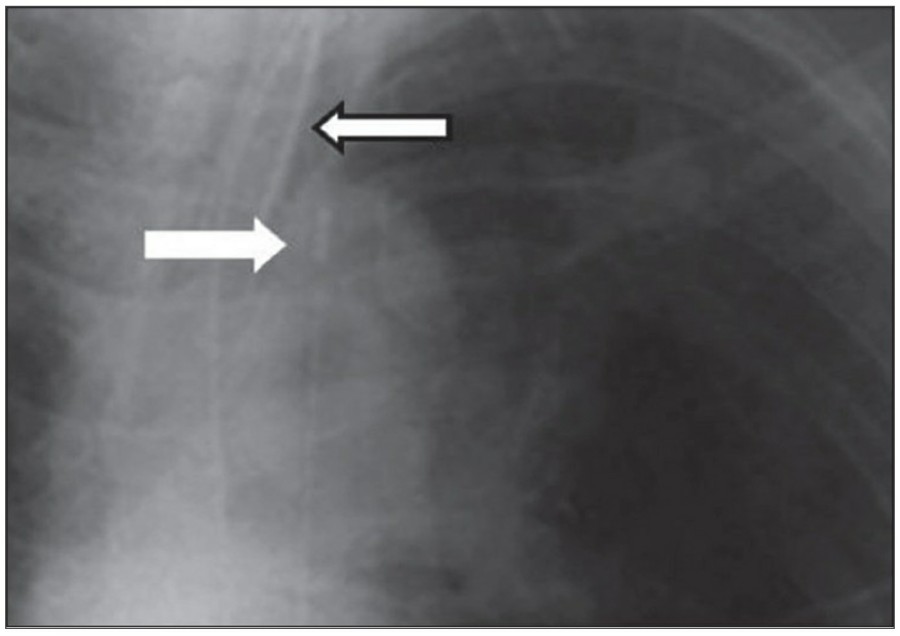

또한 Mediastitnal air는 major airway 손상으로 인한 leakage나 retroperitoneum으로부터 fascial plane을 따른 air dissection에 의해 발생하기도 한다. Pneumomediastinum은 목까지 공기가 진행이 가능하고, pneumopericardium은 이와는 다르게 심장의 밑 부분으로 진행한다. Pneumomediastium은 일반적으로 무증상이지만, 간혹 청진 시 restrosternal crunch가 들릴 수 있다. Chest X ray상에서 공기가 major vessel 주변이나 SVC의 medial border, azygos vein에서 surrounding lucency로 보일 수 있다. 또한 aortic knuckle, descending aorta, pulmonary artery의 윤곽으로 나타날 수도 있다. Posteromedial pneumomediastinum은 주로 esophageal rupture의 결과로 나타날 수 있는데, praspinal costophrenic angle과 left diaphragm의 praietal pleural로 air dissection이 가능하다. 이 결과 V-sign of Naclerio라고 불리는 V-shaped lucency가 발생한다.